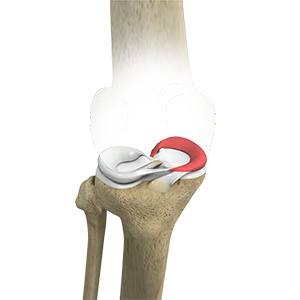

Picture of Lateral Meniscus Syndrome

Lateral Meniscus Syndrome

The knee joint is formed by the union of two bones, namely the femur (thigh bone) and the tibia (lower leg bone). At the junction of these two bones is a cartilage called the meniscus, which acts as a shock absorber. There are two menisci – the lateral and medial menisci. The lateral meniscus is the outer meniscus of the knee joint and gives a cushioning effect during weight bearing activities.